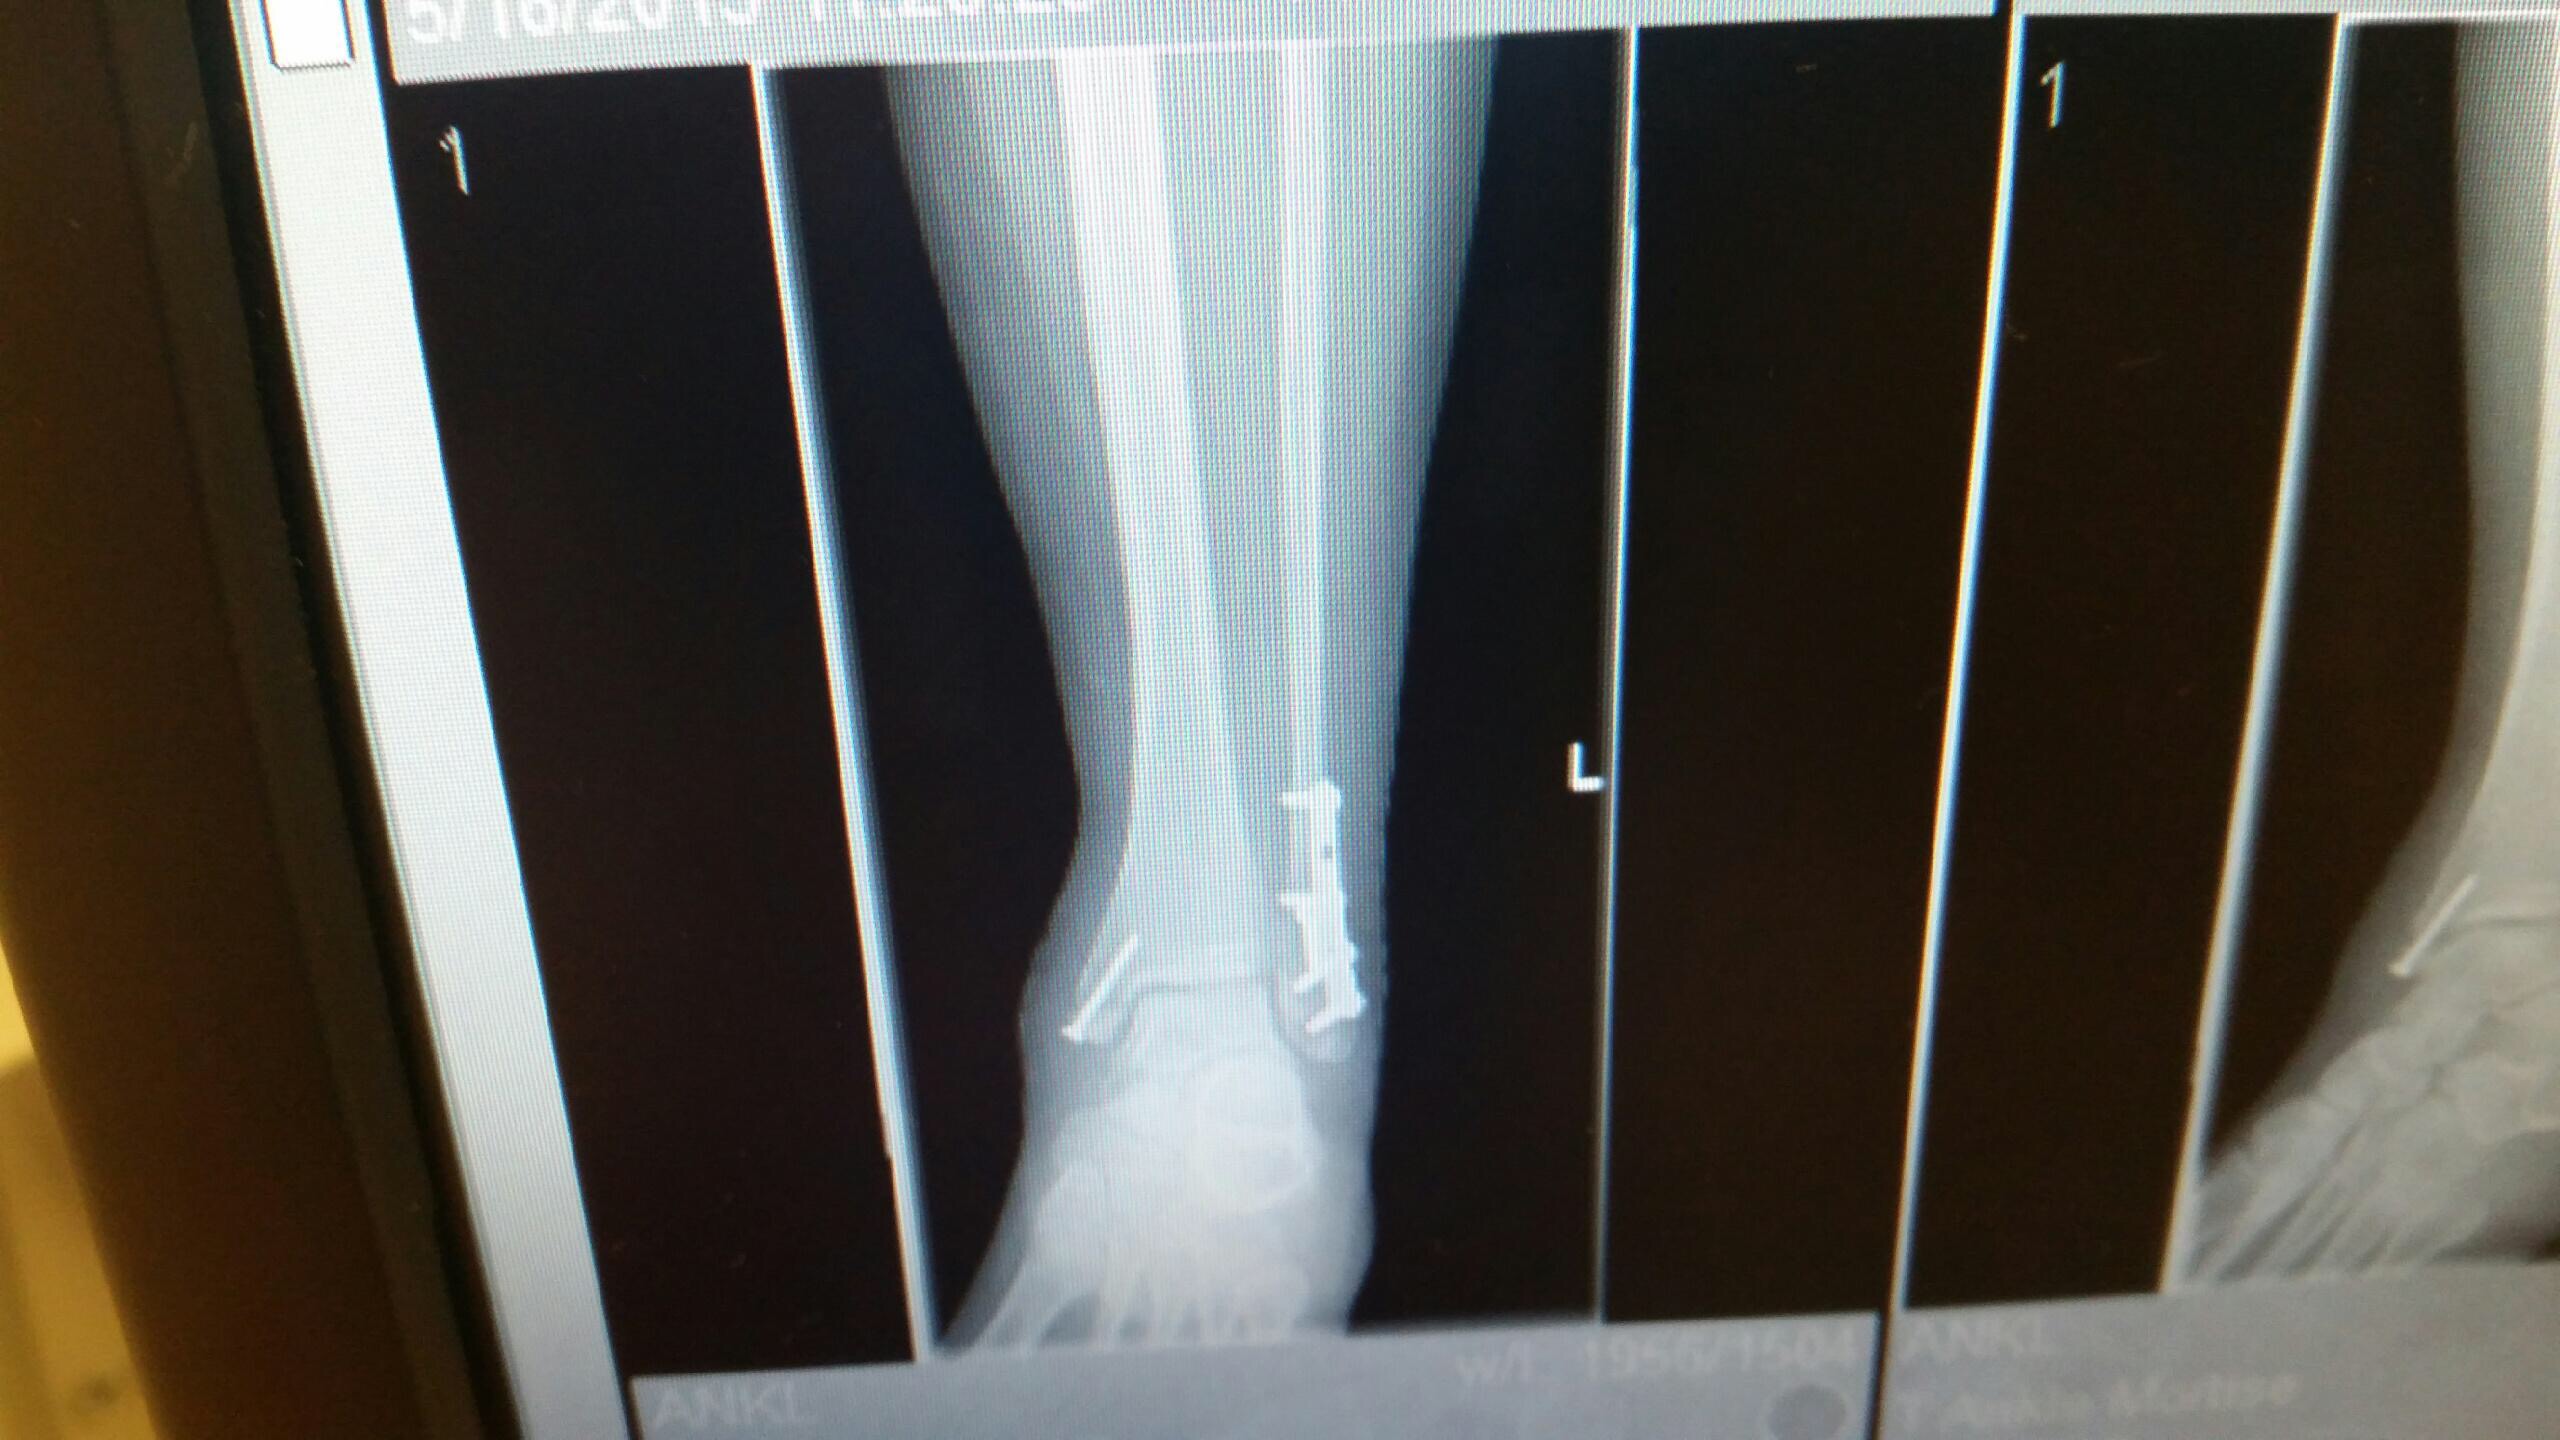

The cast is off! I can’t walk on my ankle for two more weeks, but I can move it a bit. The stitches were removed and I can get the incisions wet and everything! There were twelve stitches on the outside and six on the inside of my ankle. The swelling and bruising isn’t as bad as I thought it would be. It’s kind of scary to have this unprotected ankle, but encouraging to see how much I can move it. I feel like I’m really making progress.